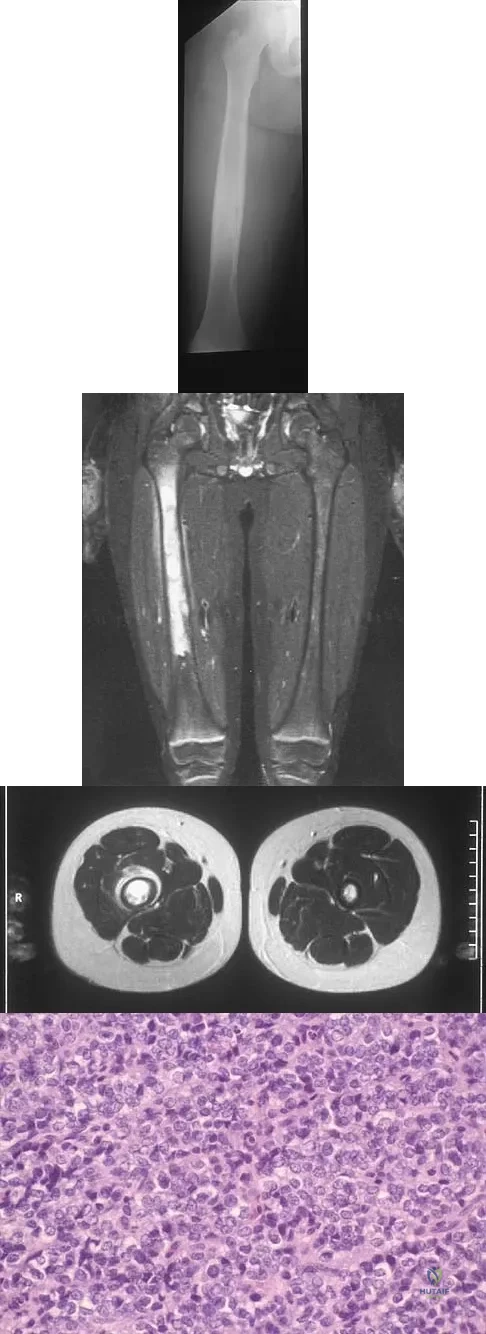

A radiograph, MRI scans, and a biopsy specimen of a 9-year-old boy with thigh pain are shown in Figures 37a through 37d. Management should consist of